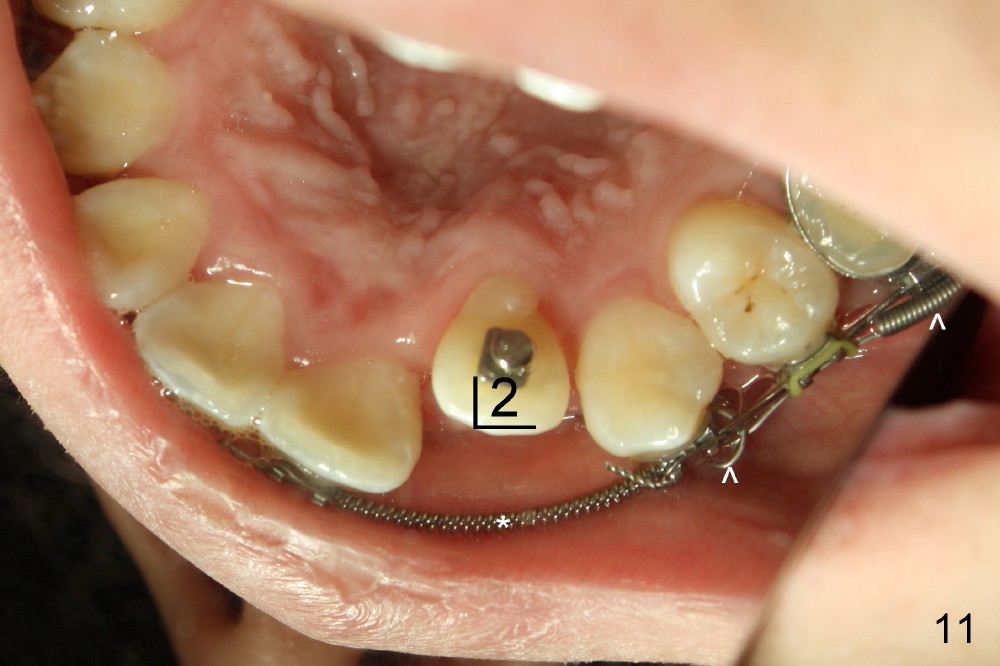

One month of closed coil spring (150 gms-9mm) (Fig.10 >, mirror image) results in the closure of the space between UR3 and 5. At the same appointment, there is enough space for UL 2 (Fig.11, mirror image). Notice the rotation of UR 3 due to retraction of the closed coil spring (Fig.10). It is immediately corrected when a rotation wedge is placed on the mesial of UR3 (Fig.12 *). However, there is an instant separation of UR 3 and 5. The closed coil spring has to be used (Fig.12>).